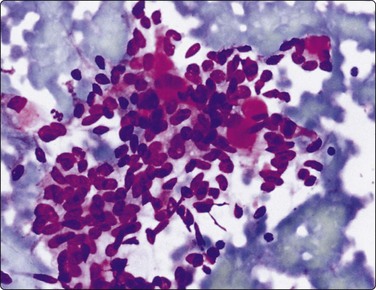

image

Fig. 4.6 Squamous cell carcinoma

Mainly poorly differentiated malignant cells with large vesicular nuclei and large nucleoli; a few squamous and keratinized cells. FNB smears of cervical lymph node metastasis from squamous carcinoma of larynx (A, MGG; B, Pap, HP).

Squamous cell carcinoma (SCC) is by far the commonest type of carcinoma encountered in the head and neck. Diagnostic criteria are listed in Chapter 8. Lymph node metastases of well-differentiated squamous carcinoma, particularly those arising in the Waldeyer’s ring, have a tendency to undergo liquefactive degeneration (see Fig. 4.3).41 The existence of primary SCC arising in a pre-existing branchial cyst has been doubted and is, in any case, an extremely rare event.42 The distinction from non-neoplastic cysts, mainly branchial cysts has been discussed above. Non-keratinizing squamous cell carcinoma may be represented in smears mainly by small basaloid cells in which case the differential diagnosis includes basal cell carcinoma, pilomatrixoma, poorly differentiated adenoid cystic carcinoma and other small cell tumors. Cells from a poorly differentiated squamous cell carcinoma have large vesicular nuclei and macronucleoli and resemble other anaplastic tumors such as melanoma and large cell lymphoma (Fig. 4.6).